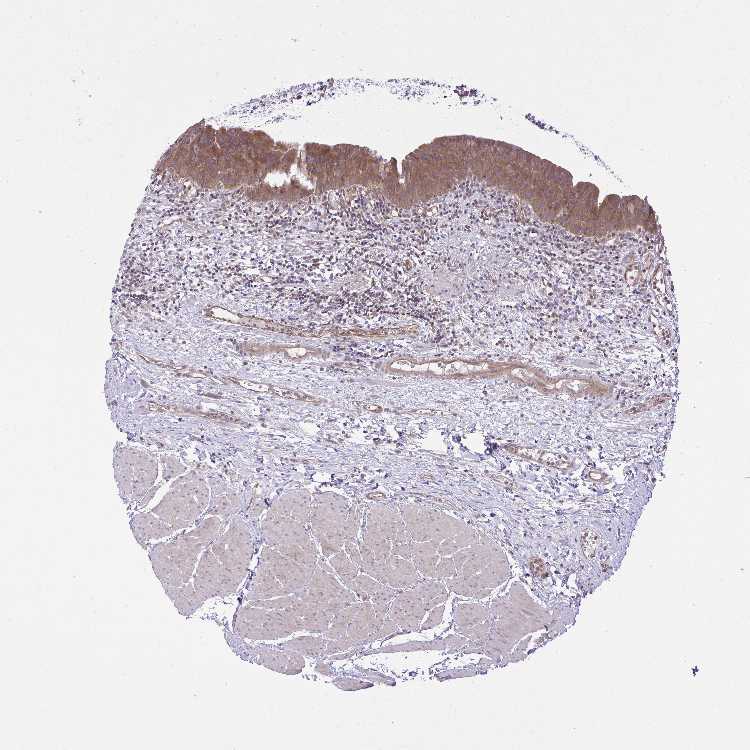

TISSUE PRIMARY DATA URINARY BLADDER Show tissue menu

Urinary bladder

URINARY BLADDER - Antibody stainingi

Antibody staining in the annotated cell types in the current human tissue is reported as not detected, low, medium, or high, based on conventional immunohistochemistry profiling in selected tissues. This score is based on the combination of the staining intensity and fraction of stained cells.

Each image is clickable and will lead to virtual microscopy that enables deeper exploration of all samples and also displays staining intensity scores, fraction scores and subcellular localization as well as patient and tissue information for each sample.

Antibody HPA029065Antibody HPA056933Antibody CAB022641

Urothelial cells LowMediumMedium